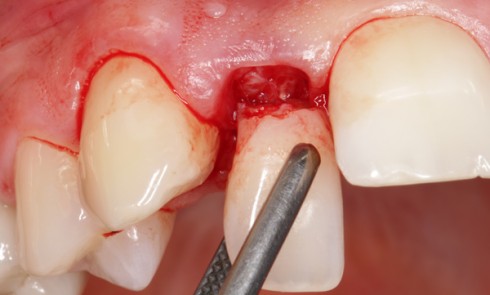

Article réservé à nos abonnés La prise en charge en urgence de l’abcès parodontal

1. Diagnostic L’abcès parodontal correspond à une inflammation purulente, le plus souvent aiguë et localisée, entraînant une destruction rapide des...